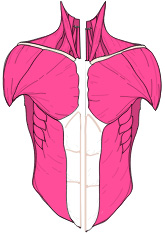

Die Muskeln benötigen die Knochen-Hebel als Kraft-Übersetzung.

Befindet sich Spannung und Gegenspannung nicht im Gleichgewicht, verzieht es das Skelett. Dadurch verändern sich Knochen- und Gelenkstellungen, was zu einseitiger Überbelastung führt und vielmals als Arthrose betrachtet wird.

Diese Fehl-Spannungslinien verursachen Überdehnungsschmerzen, Durchblutungs- und Lymphsystem-Störungen. Die Spannungslinien führen auch zu inneren Blockaden von Organen, Organ-Verbindungen, die wiederum unterschiedliche Beschwerden verursachen können.

Im Wissen, das sich kein Skelett aus eigenem Antrieb bewegen kann. Für den Zusammenhalt der Knochen, Gelenke, Wirbelkörper und die Bewegung sind die Muskeln, Sehnen und Bänder verantwortlich.

Muskulatur / Sehnen und Bänder

Muskulatur, Sehnen und Bänder sind für die Bewegung und den Zusammenhalt des Skeletts verantwortlich. Die Muskeln benötigen die Knochen als Kraftübersetzung. (ein gesunder Mensch ca. 656 Muskeln)

Weil sich Muskel/Sehnen Ansätze zur optimalen Kraftübertragung häufig in Gelenk- und Wirbelnähe befinden, werden die Muskel / Sehnen Überdehnungen vielmals als Gelenk oder Rückenbeschwerden / Schmerzen wahrgenommen. Die Summe der Fehlspannungen und deren Ausweichhaltungen führen so automatisch zu Belastungs-, Durchblutungs- und Funktions-Störungen, die sowohl das Skelett, als auch die Muskulatur Linien und dadurch auch innere Organe und Organverbindungen betreffen können.